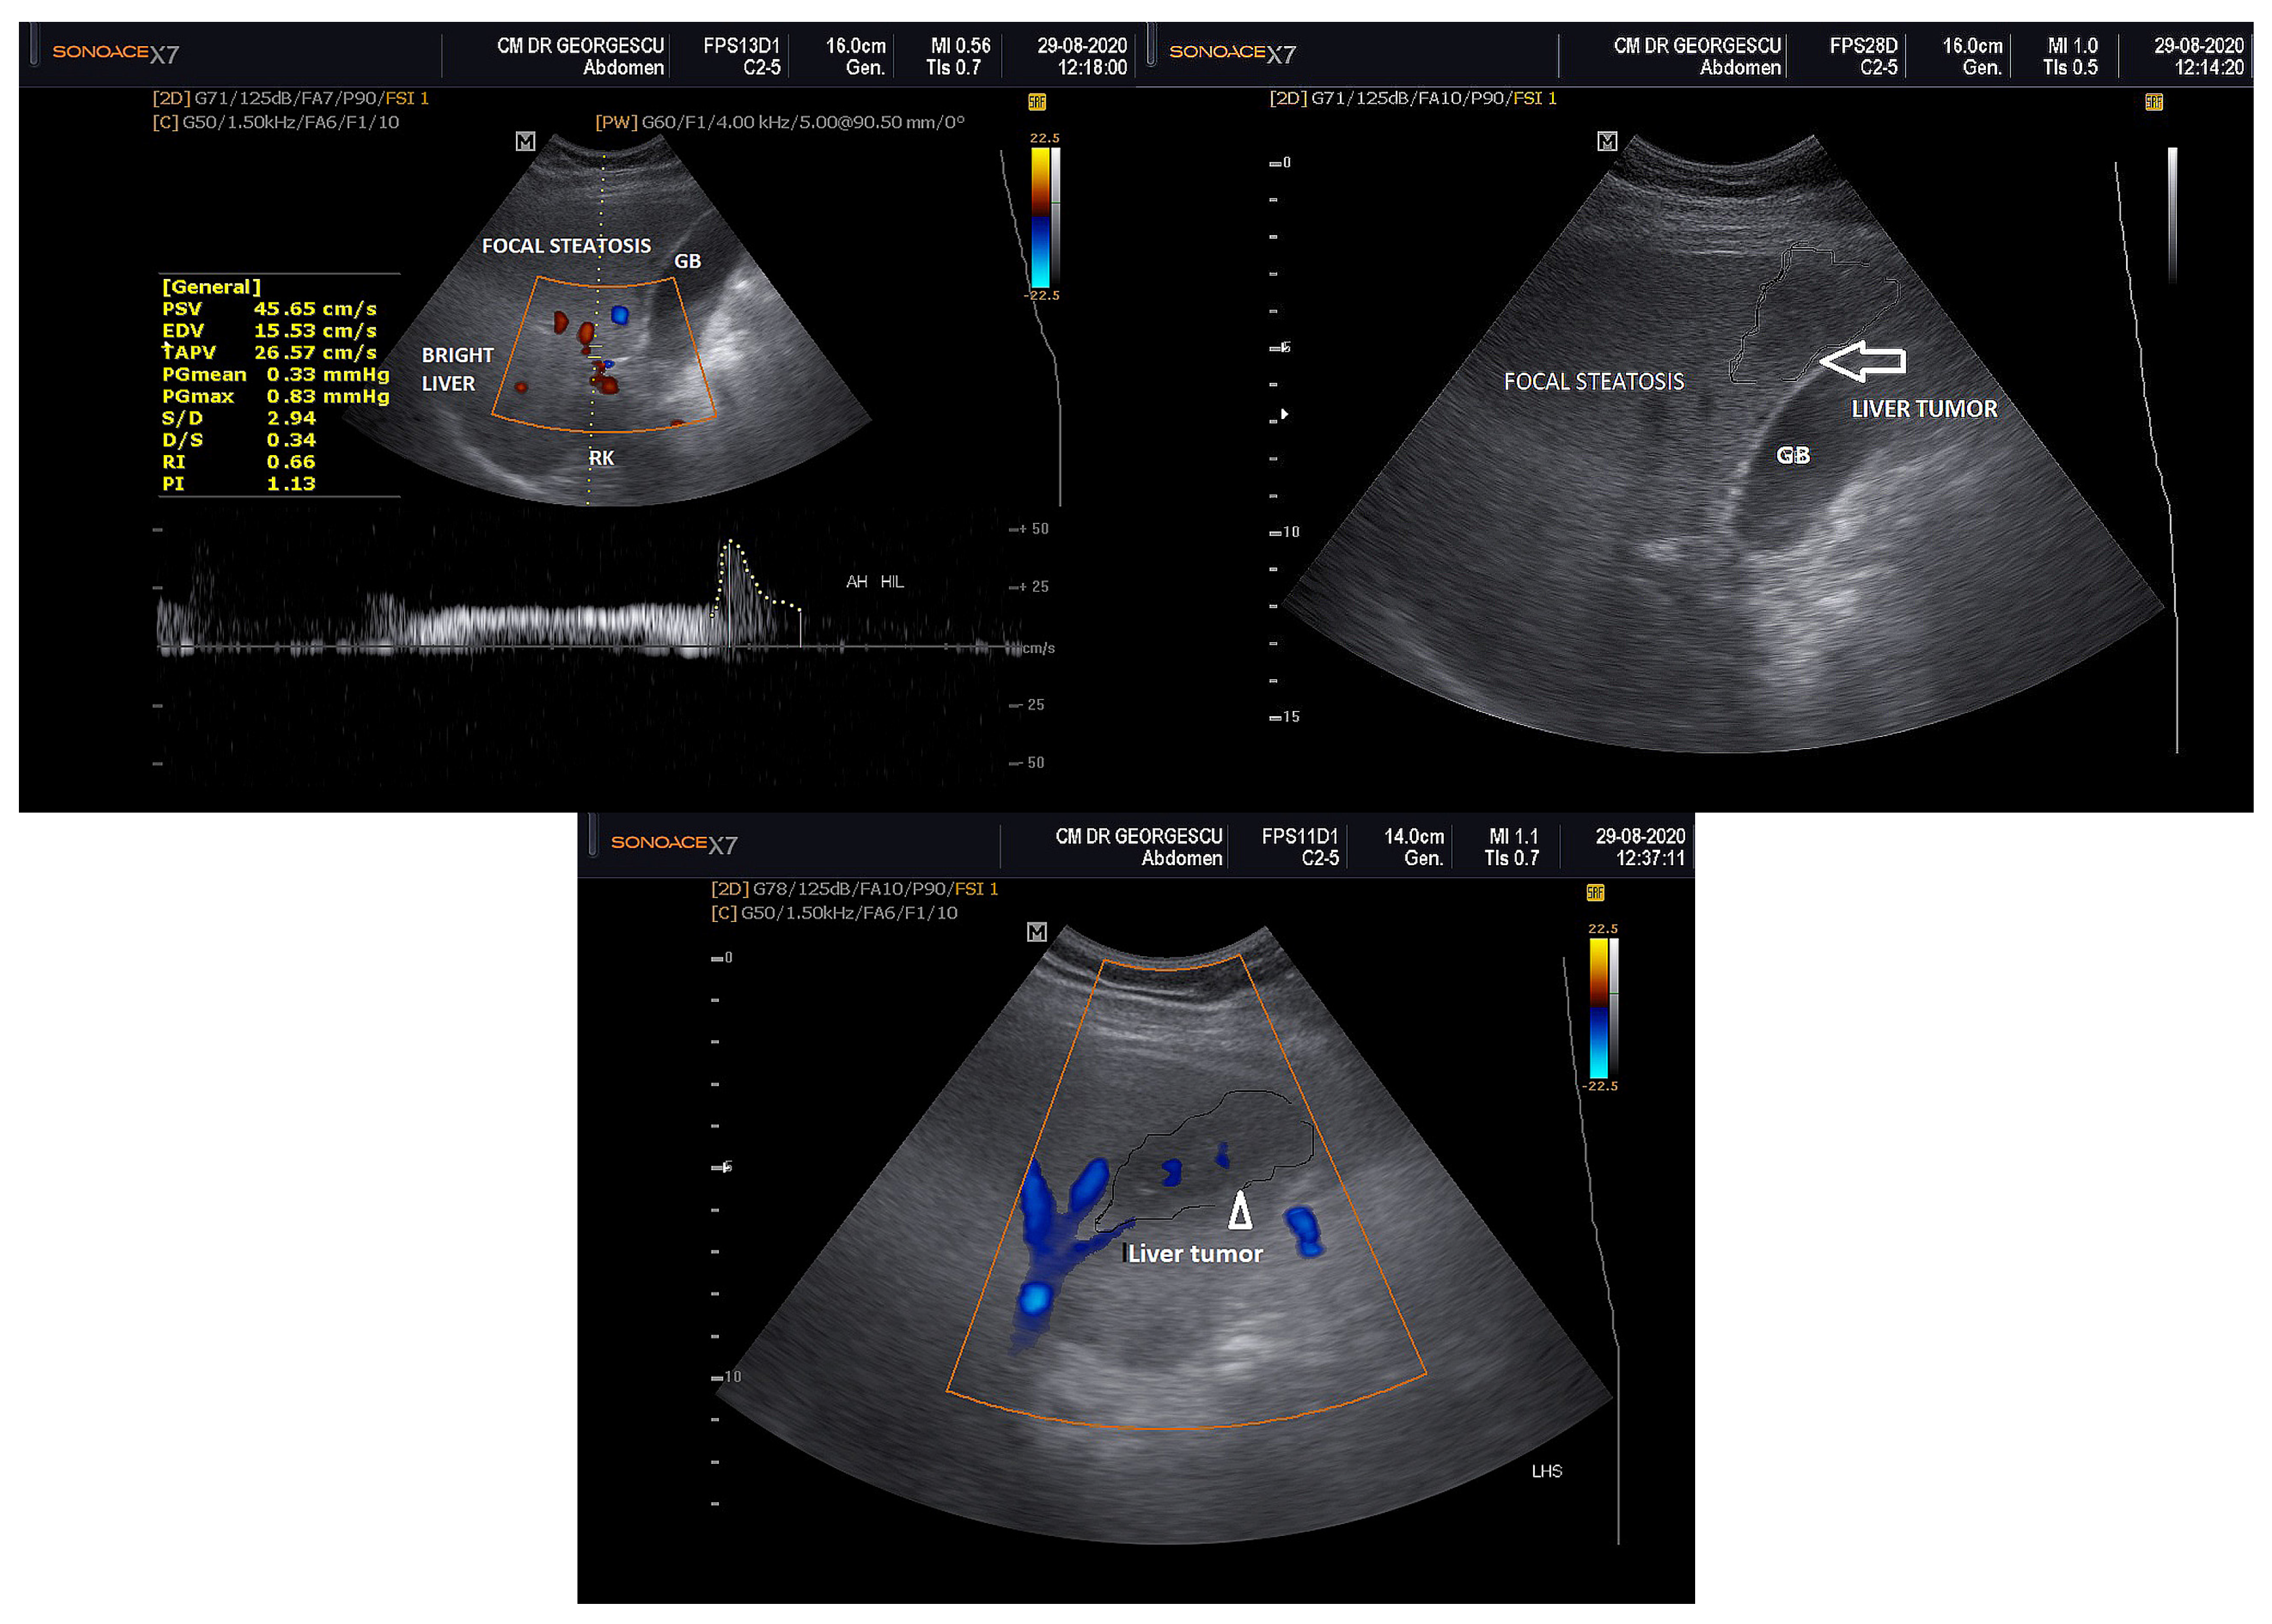

2. Case Report